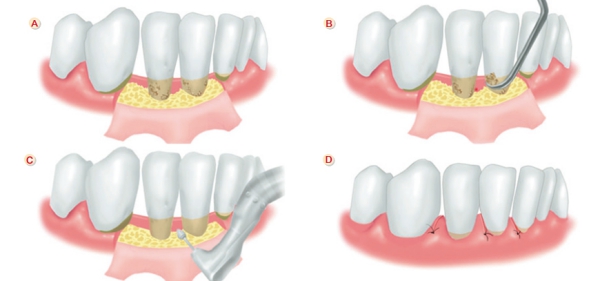

第二階段:牙周手術評估

進行牙周的第一階段基礎治療後,需再回診由醫師檢查牙周恢復狀況,若第一階段治療後問題沒有改善,就會評估進行第二階段牙周手術,幫助去除牙周囊袋較深層的牙結石。牙周手術包含「牙周翻瓣手術」,也就是將牙肉翻開,讓醫師刮除發炎組織,並徹底的清除牙結石,再進行傷口的縫合。若是齒槽骨已出現缺損,則可以透過「牙周再生手術」,放置牙周再生材料如骨粉,重建喪失的骨頭。牙周手術只要在局部麻醉的情形下即可進行,不需要住院,治療後的照護也不影響日常生活。